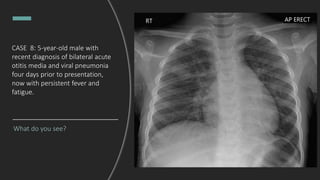

CASE 8: 5-year-old male with

recent diagnosis of bilateral acute

otitis media and viral pneumonia

four days prior to presentation,

now with persistent fever and

fatigue.

What do you see?

Final Dx: Right upper lobe round

pneumonia